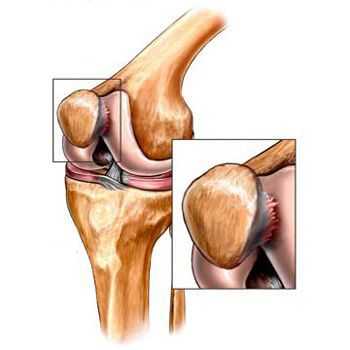

Субхондральная кость, из которой гиалиновый хрящ получает питание, при ОА также претерпевает изменения: отмечаются неровность, нечеткость, прерывистость суставной костной пластины, что показано на рисунке 4. При этом отмечается неоднородность субхондральной кости в виде гипо- и гиперэхогенных очагов. Данные изменения субхондральной кости подтверждают тот факт, что для лечения ОА желательно использование препаратов, воздействующих на костную ткань.

Рис. 4. Субхондральная костная пластина надмыщелков бедренной кости при ОА (длинная стрелка). Измененный суставной хрящ (короткая стрелка)